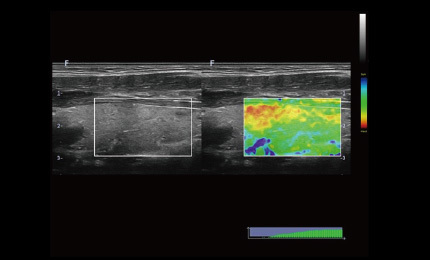

Elastografia

Elastografia w czasie rzeczywistym to nowa nieinwazyjna i bezbolesna technika, która pomaga określić twardość organów oraz innych struktur takich jak piersi czy tarczyca. Obrazowanie elastyczne dostarcza użytkownikom dynamicznych informacji wizualnych i pokazuje sztywność organów, co jest pomocne w bezpośredniej i ilościowej diagnozie oraz leczeniu.